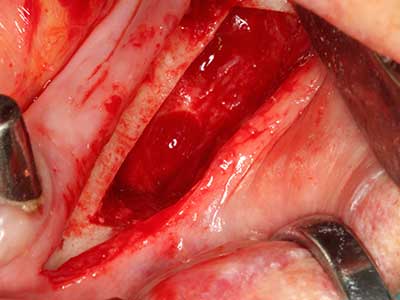

En la extracción de bloques óseos la piezocirugía también presenta ventajas adicionales: Además de la alta precisión en la osteotomía que ya se ha descrito antes, se ha comprobado que el uso de los delgados insertos de sierra resulta especialmente cuidadosas con el hueso. Frente a esto, sobre todo cuando se usan las fresas de Lindemann, cabe esperar pérdidas en la extracción significativamente más altas debido al mayor grosor de la parte frontal del cabezal (Lakshmiganthan, Gokulanathan et al. 2012). La separación basal que se necesita en particular en los injertos de bloque extraídos de forma retromolar se ve facilitada mediante sierras perpendiculares especialmente previstas a tal fin, lo que permite considerar que la cirugía piezoeléctrica es un procedimiento preciso y seguro para la obtención de bloques de hueso en el área retromolar (Happe 2007) (fig. 1-12).

Aplicación: Partición ósea / Cortical Split